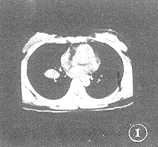

病人 女,20岁。入学体检胸部透视发现右下肺门区肿块。无咳嗽、发热、盗汗、咯血及胸痛等症状。查体无阳性发现。实验室检查未见异常。6uj, http://www.100md.com

CT扫描示:右下肺门区有一肿块向肺野内突入(图1,2),约2.6 cm×3.0 cm×3.6 cm大小,类圆形,密度均匀,无钙化和囊性变,CT值+77HU。肿块边缘光滑,无分叶及毛刺。邻近肺野未见异常,支气管未见阻断,纵隔未见淋巴结肿大。请分析何种疾病可能性大。(答案见第20页)

图1,2 右下肺门区一类圆形肿块向肺内突入,约2.6 cm×3.0 cm×3.6 cm大小,边缘光滑,密度均匀,其它肺野及纵隔未见异常■(冉崇建 陈显章)